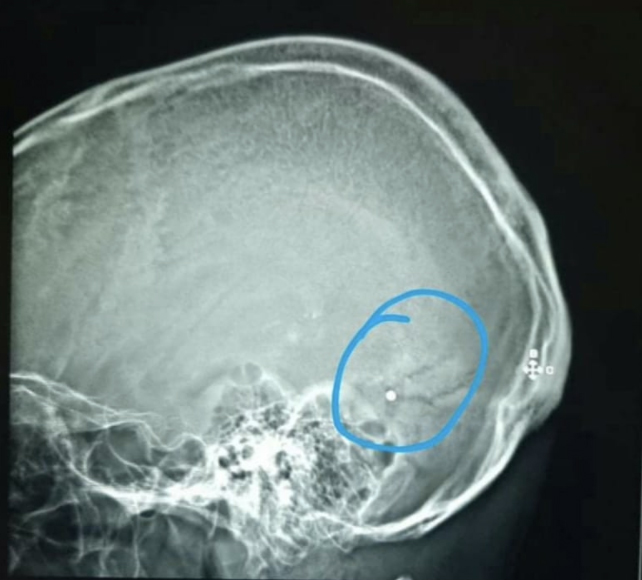

Chakhtoura said his colleague Dr Elie Saliba had been shot in the head at Saturday’s protests after working long shifts to save victims of the Beirut explosion.

Chakhtoura also noted a number of people had come in with more superficial wounds, consistent with birdshot fired from a farther distance away.